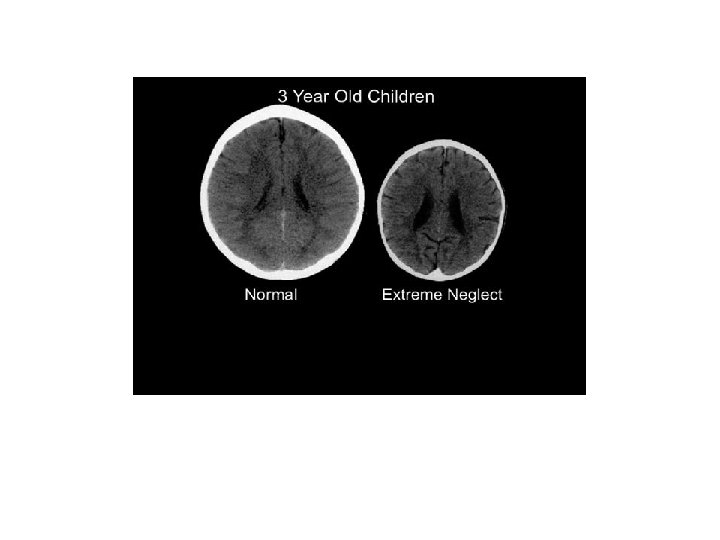

Key Points re Early Childhood Development • Biologically the brain is shaped by experience. • The importance of the “serve and return” interaction. • When children experience neglect this leads to a “wear and tear” effect. • Intervening early is important. • Neglect impairs the ability to learn as the cognitive and emotional functions of the brain cannot be separated. • The Science of Neglect

The Science of Neglect- Key Points • Children need to have responsive interactions with adults. • Neglect can cause a child to be “constantly bathed in stress hormones” • Interventions need to attune people to the serve and return process. • Harvard provide us with four levels of neglect.

The four Harvard Levels of Neglect • Occasional inattention - not concerning, may potentially benefit a child’s development. • Chronic under stimulation- Impacts on development but children will show catch up with the right intervention. • Severe neglect in a family context- not being fed/bathed etc. , puts a child more at risk of substantial deficits. • Severe neglect in institutional settings – alters the development of the brain architecture, constant change of care givers.

Ward and Brown • Severely suboptimal and abusive parenting during the first 3 years of life has a disproportionately large impact on the infant/toddler brain. • Helps us to understand the extensive evidence about emotional and behavioural development of very young children. • For example, the persistent fear response, hyperarousal, dissociation and disorganised attachments that have been widely identified • Harriet Ward – Decision Making within a Child’s Timeframe- You Tube.

Counter argument – Wastell and White • Without details of case history for the neglected child, such an image is meaningless; perhaps the child was the subject of trauma, or disability. We simply do not know. • Mythological version of the infant brain is fast becoming part of the policy and practice. • Easily invoked to profound rhetorical and material effect. • Debate regarding how well the brain can recover from neglect- e. g. Romanian orphans.